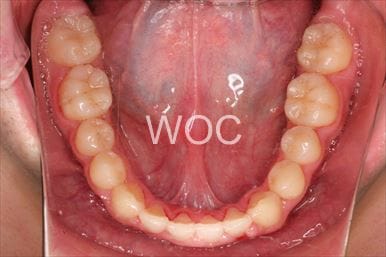

八重歯・叢生マウスピース型(カスタムメイド)矯正装置(インビザライン)

マウスピース型(カスタムメイド)矯正装置(インビザライン)を希望。ガタガタ(叢生)が強く上顎両側第一小臼歯抜歯か非抜歯のボーダーラインケースだったが、装置装着時間の協力も良く非抜歯で終了となりました。

- 年齢:35歳女性

- 主訴:ガタガタ

- 基本矯正料金:88万円

- 治療期間:2年6ヶ月

- 非抜歯

-